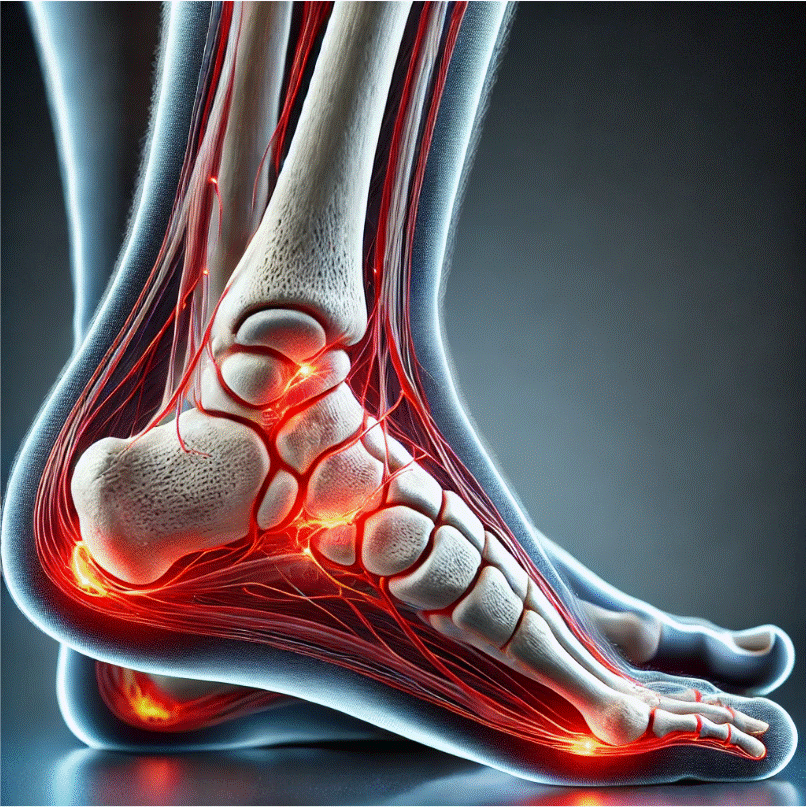

Barefoot running y fractura por estrés: impacto de la presión plantar

El barefoot running, o correr con calzado minimalista, ha ganado popularidad en los últimos años debido a sus supuestos beneficios sobre la técnica de carrera y la prevención de lesiones. Sin embargo, diferentes investigaciones han demostrado que esta práctica puede aumentar la presión plantar en la zona del antepié, elevando así el riesgo de sufrir […]